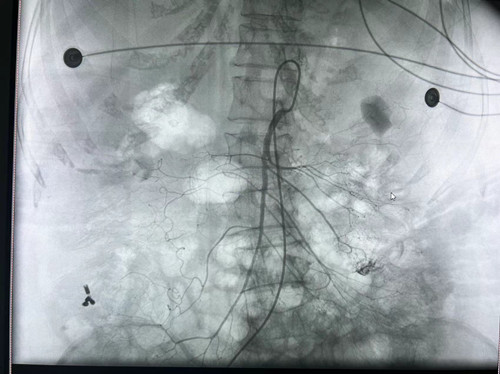

术中,梁琪副教授通过丰富的临床经验判断,与骆雷医生、唐弘喆技师配合,运用Seldinger技术,经右股动脉-肠系膜上动脉成功建立轨道,行肠系膜上动脉造影见空回肠动脉两支小分支远端造影剂呈点片状外漏至肠腔,再沿轨道顺利送入微导管及弹簧圈、可控弹簧圈成功实施栓塞。期间,为了让患者保持清醒,黎姿护士不间断呼喊患者名字,并有条不紊地配合医生工作,及时大声播报生命体征。栓塞后再次造影显示,出血动脉分支远端对比剂外溢未见显示,呈栓塞术后改变,未见异位栓塞征象,达到预期治疗效果。